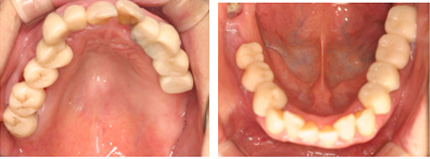

患者様はお口の状態が非常に悪く悩んで当院に来院しました。

虫歯・歯周病・咬み合わせの崩壊など問題点が多くありました。

![]() |

初診時 |